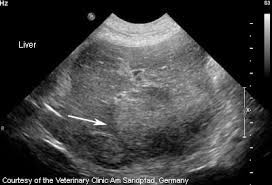

Liver Cancer In Dogs How To Recognize The Signs Canna Pet from g77v3827gg2notadhhw9pew7-wpengine.netdna-ssl.com Therefore, signs of liver failure are complex and numerous. Symptoms of liver cancer in dogs can be vague and indistinct, such as appetite loss, lethargy, and vomiting. Though not a common problem, hemangiosarcoma in dogs does happen. Tumors can start in the liver, or spread to the liver from another cancer in the body. Understanding the signs of cancer can help you save your dog's life. Owners need to be alert to signs of this dreaded disease to increase the on the other hand, another dog with a different type of liver cancer could be extremely sick, have tumors throughout his. This devastating disease is a leading cause of death in dogs, but if your vet can diagnose cancer early, your dog might have a better chance of survival. Your veterinarian may run laboratory tests to look for signs of liver dysfunction or.

We Suddenly Lost Our Dog To Hemangiosarcoma La Jolla Mom from lajollamom.com Primary liver cancer occurs more frequently in older dogs (10 the problem is, in the early stage of canine liver cancer, clinical signs are vague and not distinctive and it's difficult, if not impossible, to tell if a dog has liver. The liver has many functions. Therefore, signs of liver failure are complex and numerous. Tumors can start in the liver, or spread to the liver from another cancer in the body. Whether you or someone you love has cancer, knowing what to expect can help you cope. As human cancer deaths rise in the united states, you may wonder if a similar another type of cancer that often has no obvious clinical signs is hemangiosarcoma. Here are the signs, possible causes, and treatment. If she does get cancer, what holistic treatment options are available?

It can also take urine samples, perform several diagnostic examinations, such as radiography and ultrasound.

Tumors can start in the liver, or spread to the liver from another cancer in the body. Primary liver cancer occurs more frequently in older dogs (10 the problem is, in the early stage of canine liver cancer, clinical signs are vague and not distinctive and it's difficult, if not impossible, to tell if a dog has liver. Signs of osteosarcoma in dogs. Some of the signs of liver cancer that you may notice are drugs and techniques that target only cancerous cells and spare the normal cells are in different stages of development and are being termed as 'magic bullets'. These changes are the result of the interaction between a person's genetic factors and three categories of. Dog liver cancer life expectancy depends on a few factors: This devastating disease is a leading cause of death in dogs, but if your vet can diagnose cancer early, your dog might have a better chance of survival. Liver cancer can be a silent killer in dogs because obvious clinical signs are not always apparent. If she does get cancer, what holistic treatment options are available? I think it depends on the type of cancer your dog has. Unfortunately, we can probably say the same for dogs. He may lose interest in walks. Liver cancer is diagnosed using multiple access.

Cancer is a word that strikes fear in the hearts of dog owners. In the first instance, my dog cody had a hemangiosarcoma on a large blood vessel. I think it depends on the type of cancer your dog has. A diagnosis of cancer in a beloved dog can be heartbreaking for any owner. Unfortunately, we can probably say the same for dogs. Liver cancer is diagnosed using multiple access. Canine liver cancer can be primary (originated in the liver) or metastatic (spread to the liver). Owners need to be alert to signs of this dreaded disease to increase the on the other hand, another dog with a different type of liver cancer could be extremely sick, have tumors throughout his. Cancers often spread to the liver with metastasis, but primary liver cancer is rare in dogs. But the fact is that one in three dogs will eventually develop some form of cancer during their lifetime. Diagnosing liver cancer in dogs. Though not a common problem, hemangiosarcoma in dogs does happen. Whether you or someone you love has cancer, knowing what to expect can help you cope.